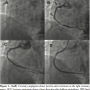

A 58-year-old man with diabetes and hypertension was admitted for angina and recurrent chest pain. He was admitted to another tertiary hospital 1 year prior for stable angina and had two Cypher stents (Cordis Corporation) implanted in the right coronary artery (RCA). No remarkable findings were observed on physical examination. His electrocardiogram, chest x-ray, and transthoracic echocardiogram were normal. Coronary angiography revealed a hazy lesion at mid-stent area suspicious of focal ISR or late stent thrombosis at the RCA (Figures 1A and 1B). The RCA was engaged with a JR 3.5 guiding catheter (Cordis Corporation) and a 0.014-inch Runthrough wire (Terumo Medical Corporation) crossed the ISR lesion with mild resistance. After ballooning with a 3.0 x 15 mm Rjujin balloon (Terumo Medical Corporation), coronary angiogram showed immediate dissection (Figure 1C), and chest pain developed. IVUS revealed that the guidewire was located out of the distorted stent with dissection (Figure 2). We negotiated another guidewire (Choice PT; Boston Scientific Corporation) several times in vain; however, with several trials, we were able to recanalize the true lumen on IVUS between the entry door of dissection and proper inner lumen. After confirming the second guidewire in the true lumen by IVUS (Figure 2), 3.0 x 23 mm and 2.5 x 33 mm Cypher stents were deployed consecutively. Final angiogram showed an excellent procedural result and no dissecting remnant at the ISR site (Figure 1D). The patient was discharged without complications.